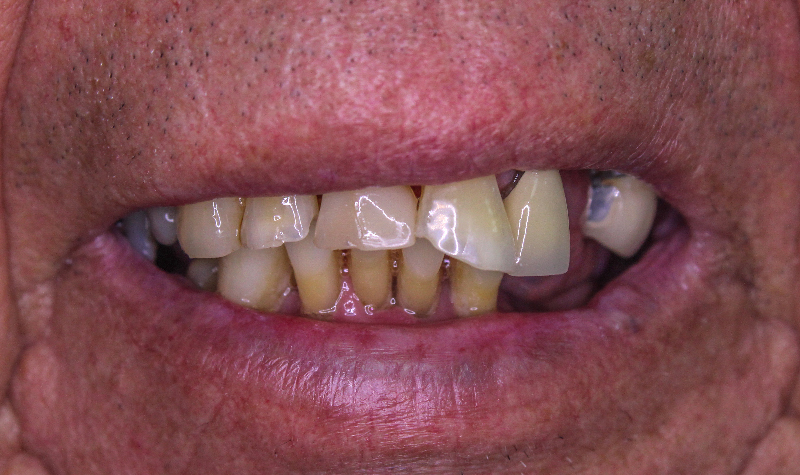

Rehabilitación Oral total con cerámicas sobre dientes e implantes.

Rehabilitación oral total de alta complejidad con cerámicas sobre dientes e implantes.

Rehabilitación oral total con prótesis inferior sobre implantes y coronas superiores.